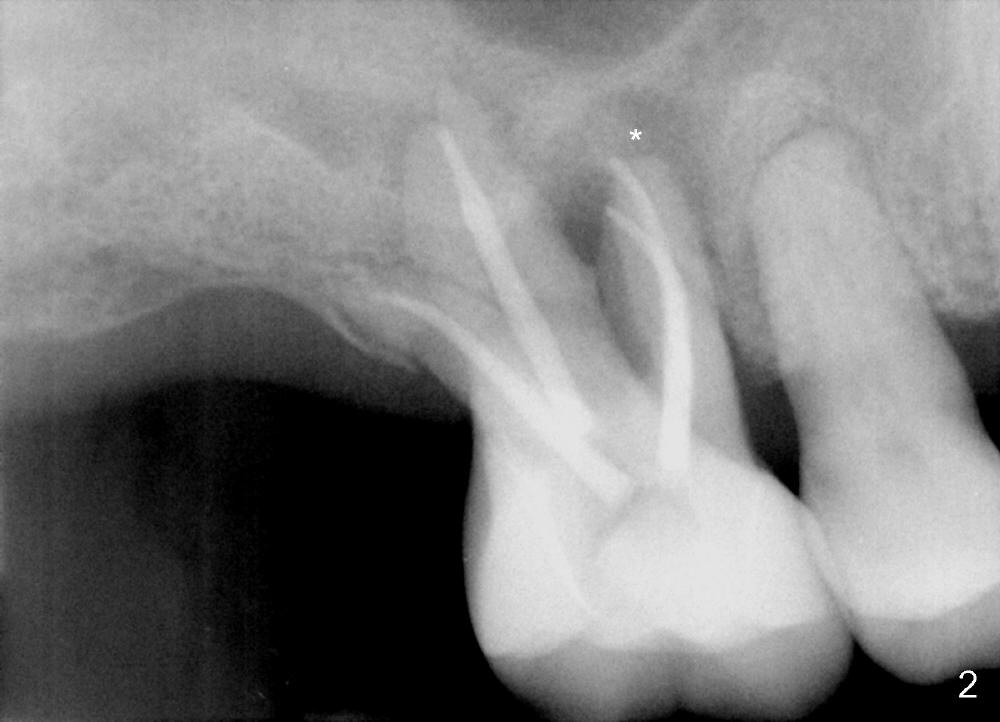

A 60-year-old man has poor dentition (Fig.1).  The tooth #3 is symptomatic with a mesiobuccal fistula.  PA shows large periapical radiolucency associated with the mesiobuccal root (Fig.2 *).  It appears that the tooth is non-salvageable.  The roots of this tooth are widely furcated.  The septum should be large unless destroyed by infection.